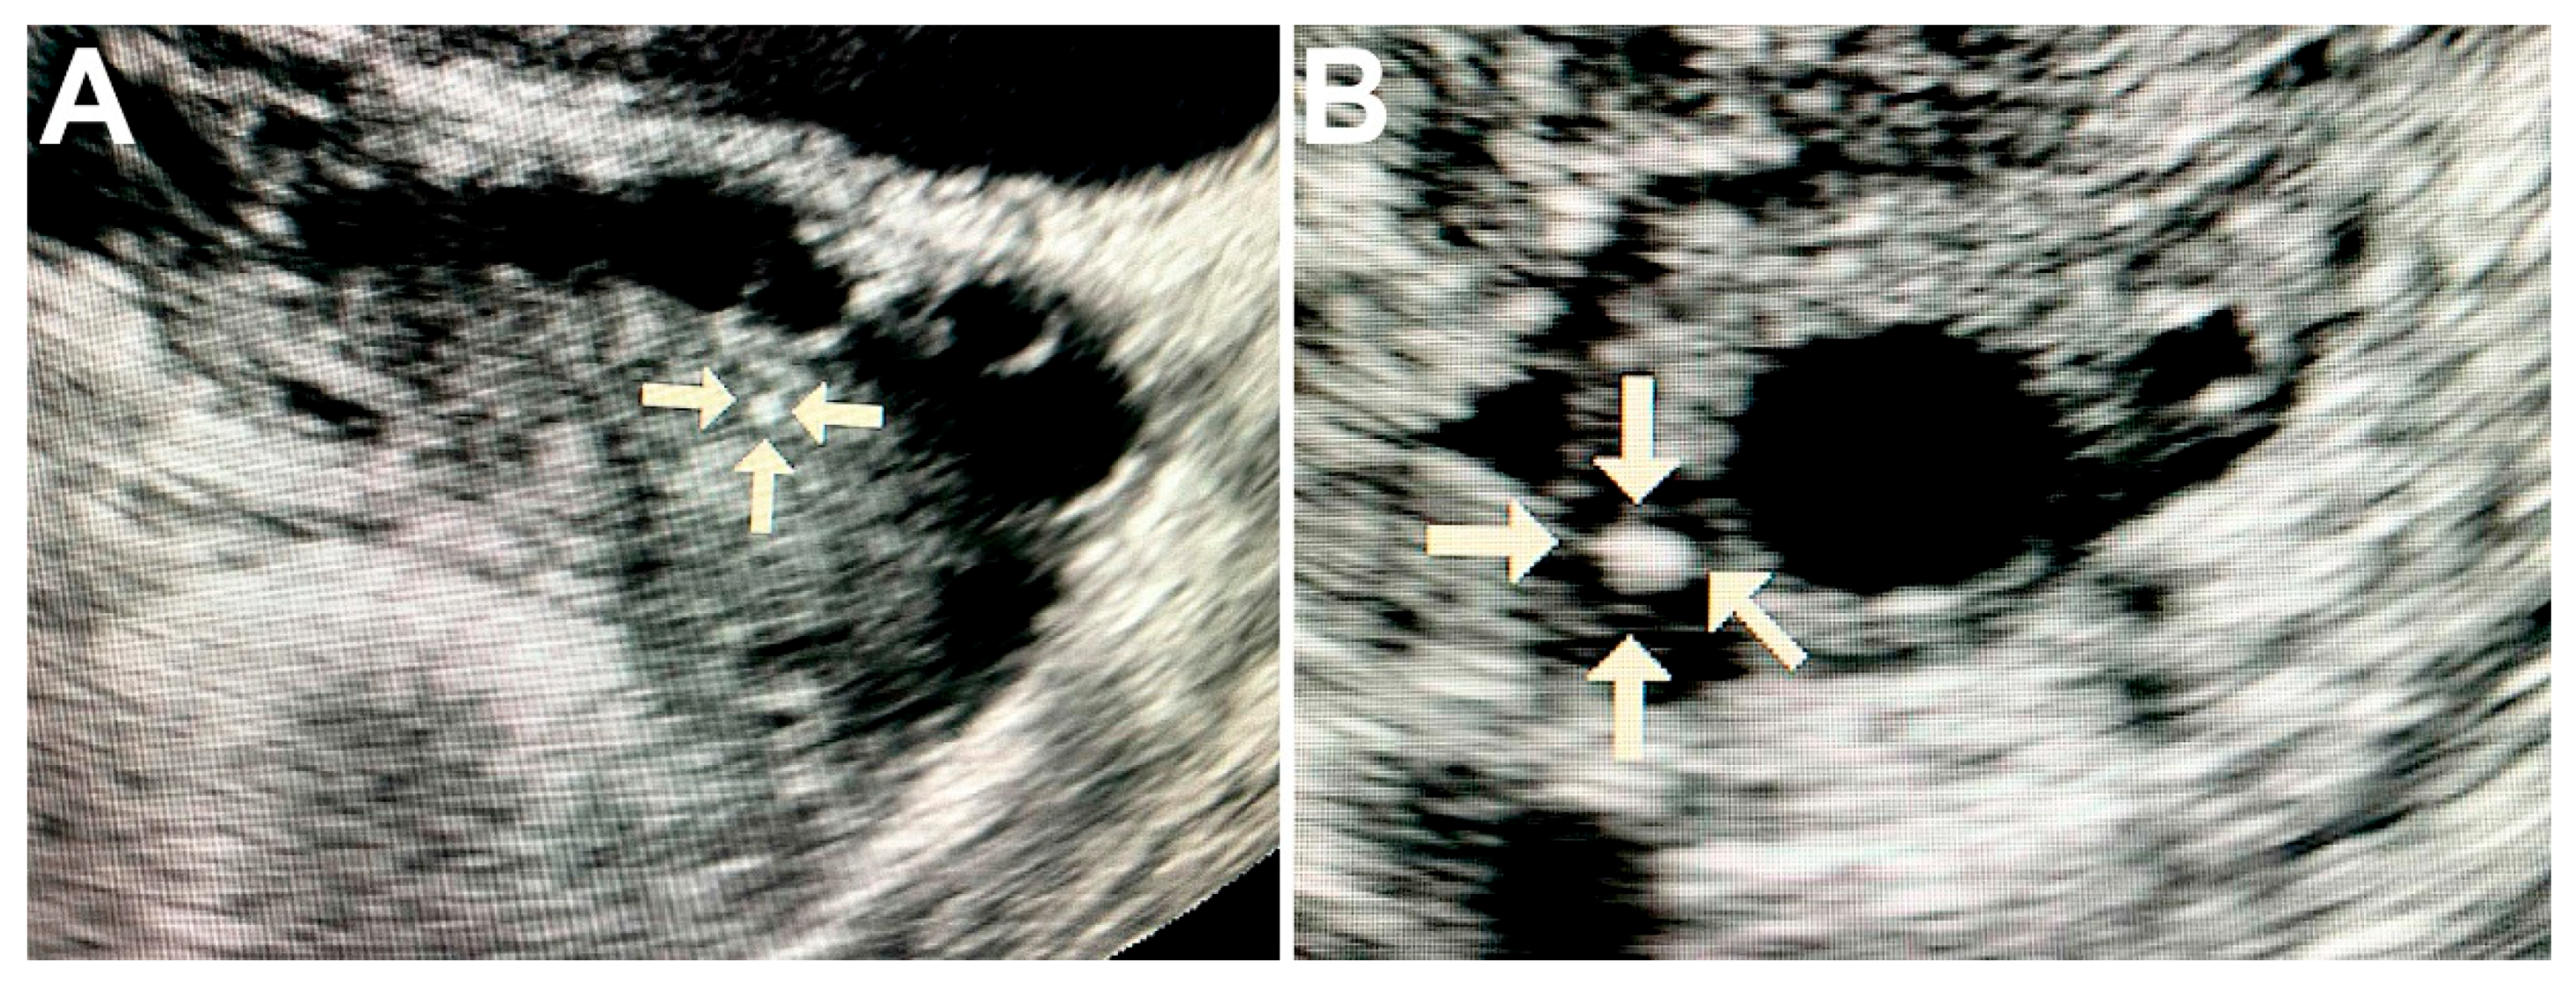

Ultrasound of ovaries with malignant tumors revealed solitary round hyperechogenic structures with smooth edges and clear contours, homogeneous echostructure and with no acoustic shadows. These formations ranged in size from 2 to 5 mm and had the avascular type of vascular pattern in the surrounding tissues (Figure 1A,B).

Figure 1.

Ultrasound image of the ovary with pathological calcifications (marked by arrows). A—rounded biomineral structure in ovarian cancer tissue; B—the calcification is surrounded by cancerous tissue with cyst formation.